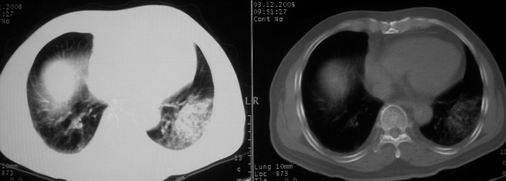

抗炎治疗一周热退,提示为炎症,现片示病灶范围增大,边缘清楚,建议继续治疗,不除外肺脓肿

炎症性病变;左侧胸腔积液。

ct左肺下叶大片状高密度影,病变密度不均,界限不清,左侧胸腔积液,治疗后复查临床症状好转而影像学表现病变有发展,还是首先考虑感染性病变,复查时间短附合感染性病变的病理改变。

两肺炎症感染(以左肺下叶为著),双侧少量胸腔积液;建议继续抗炎治疗。